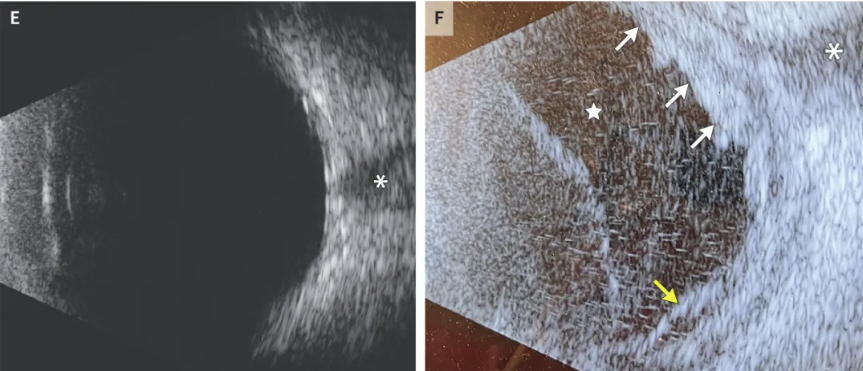

胸部X线片显示双肺可见多发斑片状及结节状阴影。增强CT检查(包括胸部、腹部及盆腔)提示双肺存在15个以上弥漫性分布的结节及肿块,多数呈空洞性,最大直径达4.4 cm,主要位于肺中叶及上叶(图1A)。肝脏可见一处囊实性病灶,直径约8.6 cm,异质性强化,并伴有肝中静脉充盈缺损(图1B)。右肺门可见直径1.4 cm的淋巴结,其他区域未见明显淋巴结肿大。头部CT未见异常。

图1. 其他医院的检查结果

静脉注射造影剂后行头部磁共振成像(MRI),显示双侧大脑半球多发皮质、皮质下及深部白质病灶,分布于不同血管灌注区,呈弥散受限(图1C);在液体衰减反转恢复(FLAIR)序列上表现为高信号,未见明显强化。右眼球轻度突出,T1加权像示右眼球内可见不规则漂浮状高信号病灶,T2加权像则显示为低信号,玻璃体内存在弥散受限病灶。右侧前眶软组织肿胀,右侧泪腺亦见水肿及强化,眼前部可见小范围积液。

体格检查见左眼外观正常,右眼眼眶周围明显水肿(图1D),眼睑轻度红肿,触压痛明显,肿胀导致眼睑无法自主睁开。右眼眼球活动受限,轻度突出,仅能感知光线。左眼眼球活动正常,视力20/60。右眼眼压为26 mmHg,左眼为17 mmHg(参考范围10~21 mmHg)。因角膜混浊及前房内纤维蛋白沉积,右瞳孔对光反射受阻;左眼瞳孔反射正常。右眼存在传入性瞳孔缺陷。裂隙灯检查右眼示全周性泡状结膜化学性水肿,角膜弥漫性水肿并见下缘上皮缺损,前房可见纤维蛋白沉积。虹膜结构模糊,仅隐约可见,晶状体完整但成像模糊,眼底结构无法观察。左眼前节正常,玻璃体清晰。散瞳后检查左眼眼底可见视网膜下方有棉絮状病灶。右眼B超提示玻璃体混浊,视网膜下方见高回声团块,同时伴明显脉络膜增厚(图1F)。